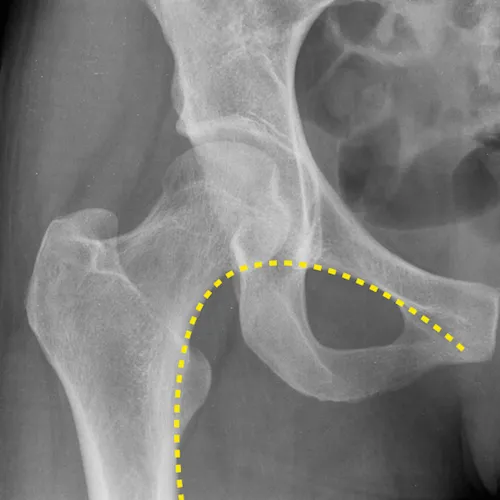

Normal Shenton line

Case courtesy of Jeremy Jones, Radiopaedia.org. From the case rID: 28928